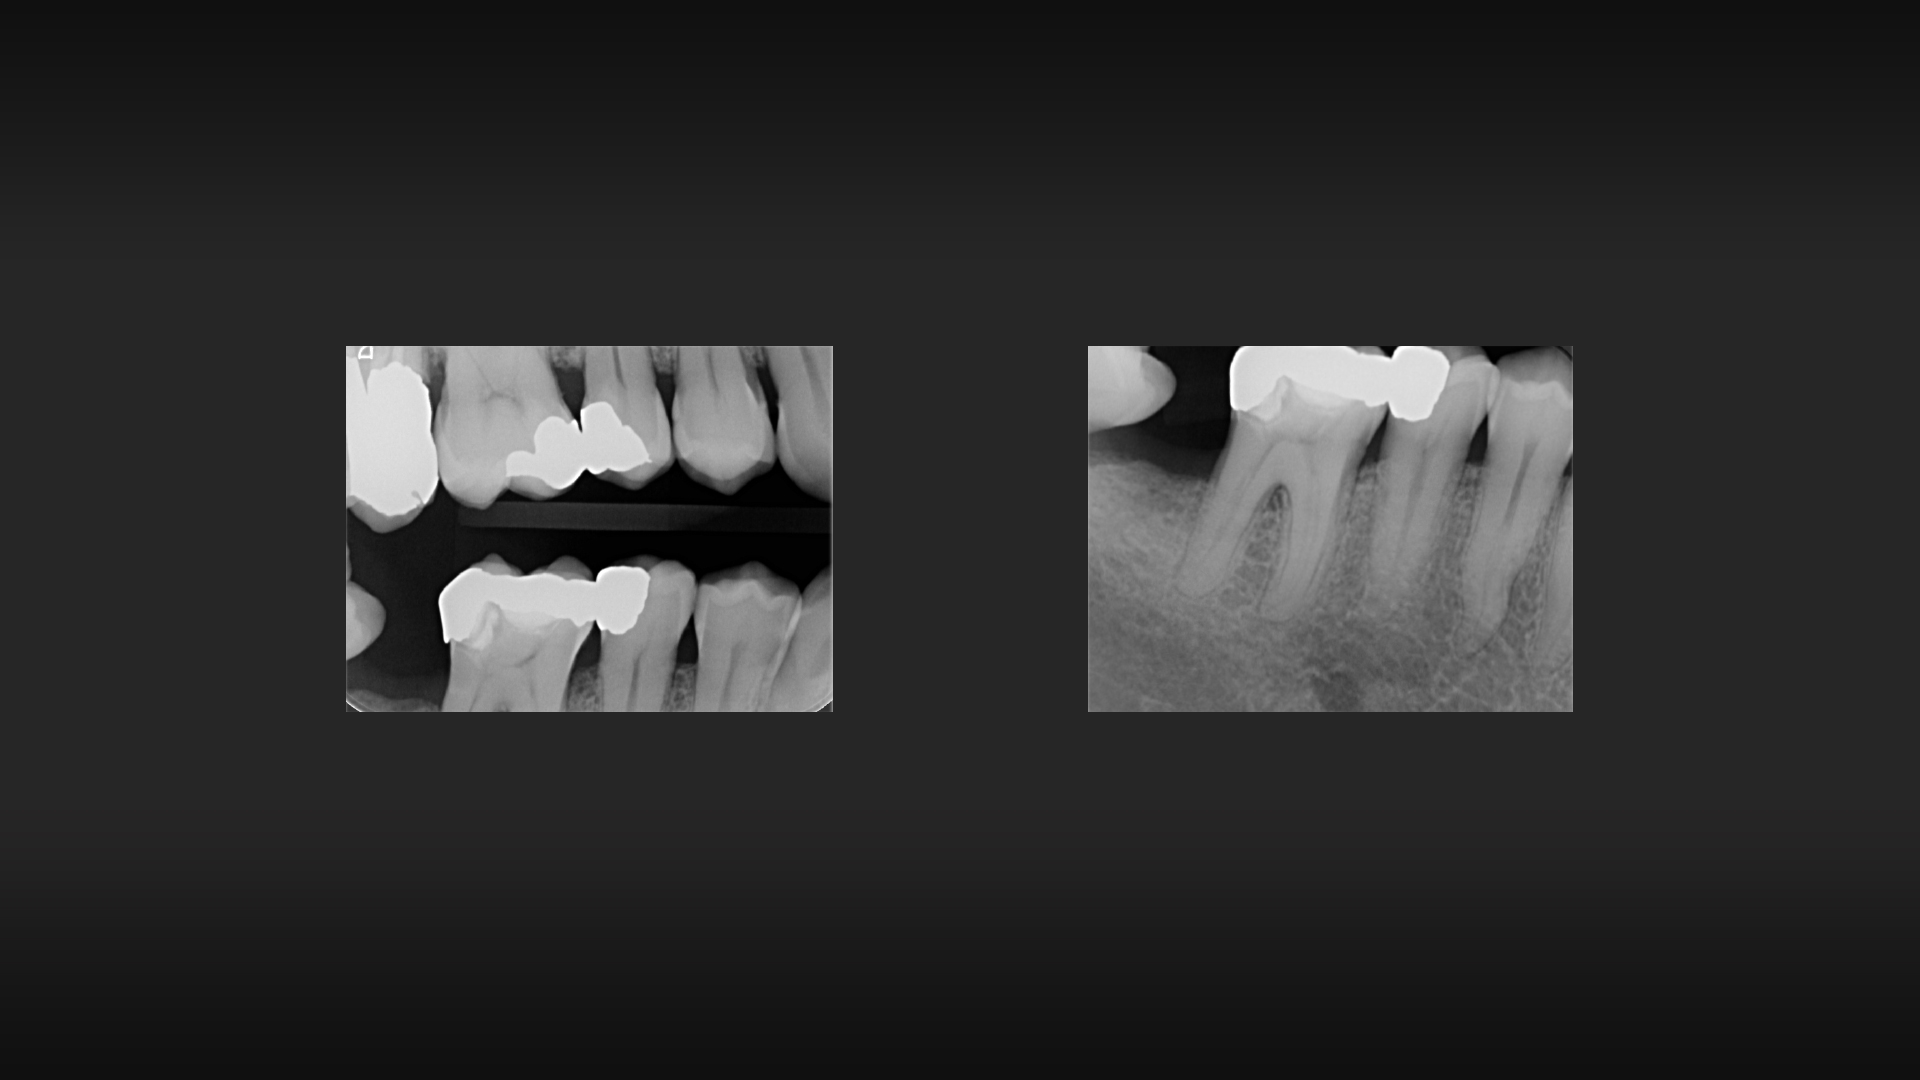

Dall’esame radiografico è risultata evidente l’incongruità del precedente restauro in amalgama e si è proceduto, dopo aver testato la vitalità dell’elemento in questione, con l’esecuzione dell’anestesia e con il montaggio della diga di gomma per l’esecuzione di un build up adesivo cui avrebbe poi fatto seguito la preparazione per un overlay in ceramica.

2. Esame radiografico iniziale